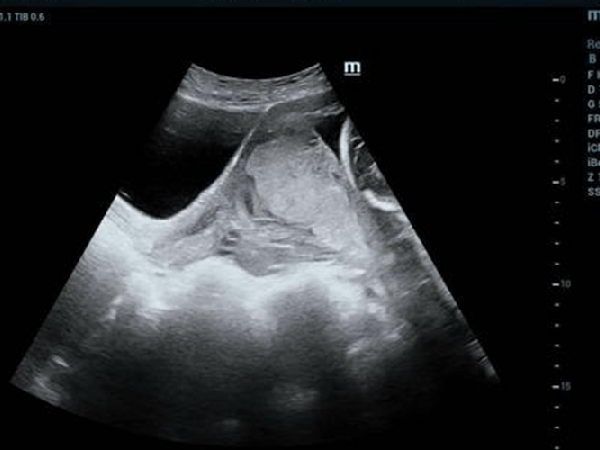

完全性前置胎盘会有大出血的风险,一般需要剖腹产手术终止妊娠,为了避免镇静药物影响胎儿,一般不会选择全身麻醉,如果孕妇有心脏病、高血压等特殊情况,医生可能会建议全麻。剖腹产手术一般是局部麻醉,全身麻醉会让孕妇和处于一个比较危险的状态,只有出现紧急情况才会全身麻醉进行剖腹产手术。前置胎盘是指胎盘附着在子宫的下半部,或者是接触子宫颈边缘的情况,前置胎盘分完全性前置胎盘、边缘性前置胎盘、部分前置胎盘三种,...

中央性前置胎盘发生难产大出血死亡率非常高,因为在妊娠晚期由于子宫不规则收缩,导致胎盘组织与子宫发生错位,导致胎盘组织完全覆盖宫颈口,胎儿在宫腔内没有充足的氧气,容易窒息,而且孕妇输血不及时,也可能导致死亡:中央性前置胎盘孕妇的死亡率中央性前置胎盘孕妇死亡率在国内报道为0.2%-1.5%,国外报道为0.5%,在中央性前置胎盘的患者中,85%到95%为经产妇,尤其是多产妇,发生率可以高达5%,与中央性...